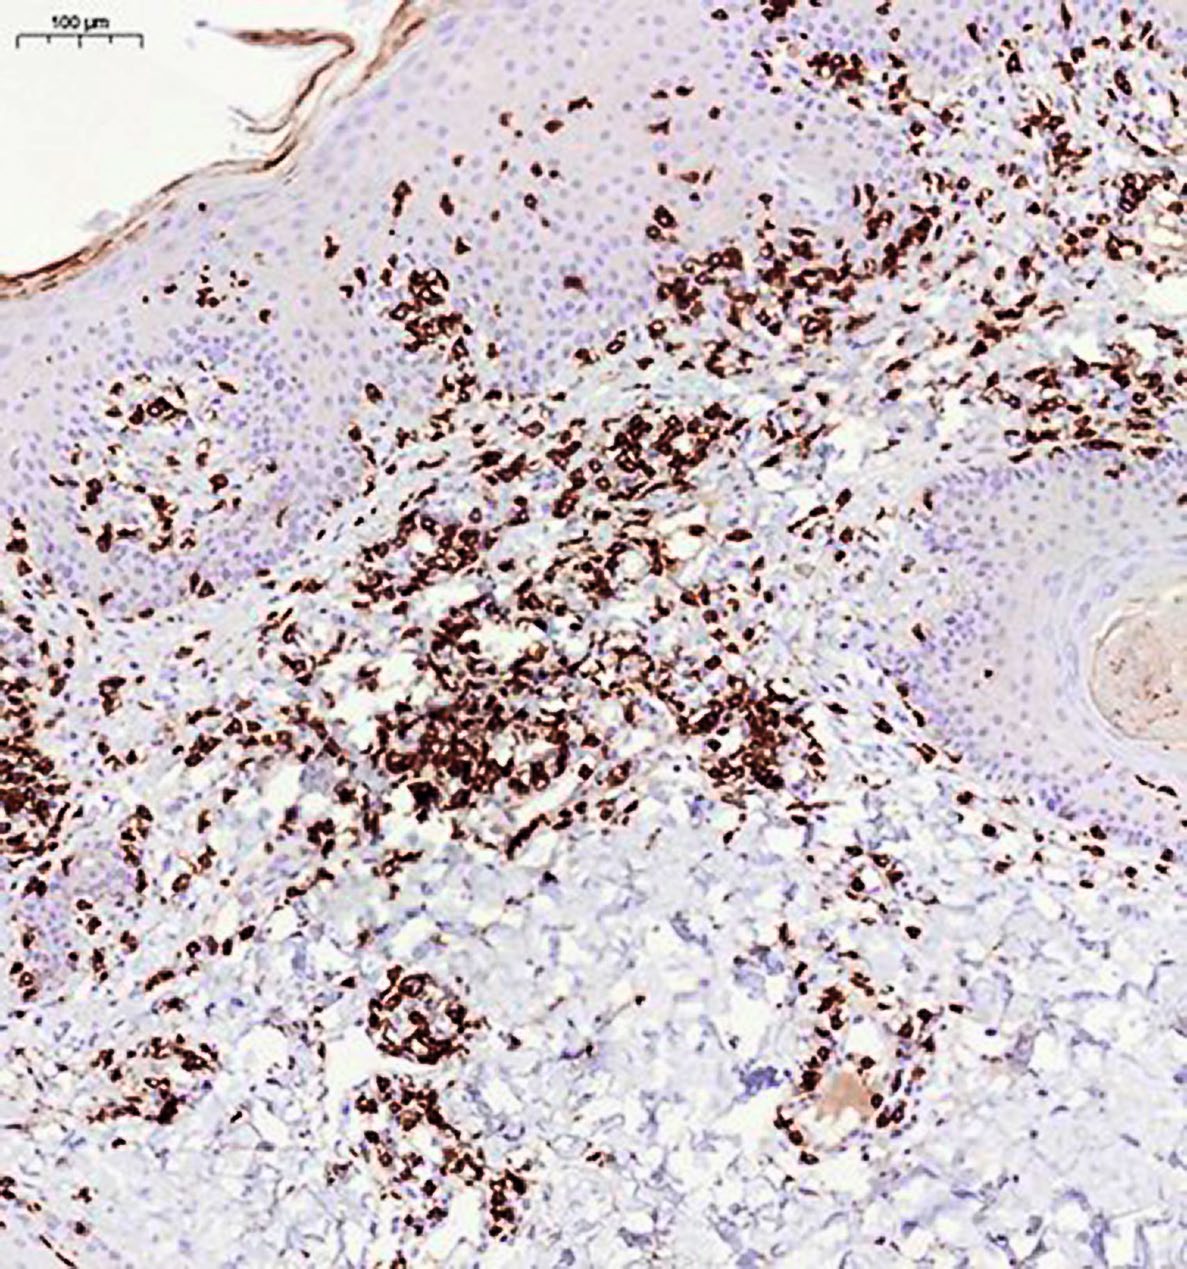

При иммуногистохимическом исследовании антиген пролиферативной активности Ki-67 экспрессирован в ядрах примерно 30% клеток воспалительного инфильтрата, в эпидермисе экспрессия Ki-67 не ограничена клетками базального слоя, а видна в более высоких слоях (рис. 5). Лимфоидные клетки инфильтрата экспрессируют CD3, CD5, соотношения CD4 и CD8 позитивных клеток соответствуют примерно 1:1 (рис. 6, 7). Единичные клетки экспрессируют CD20 (рис. 8). Заключение: клиническая картина заболевания, обнаруженные морфологические изменения в коже и результаты иммуногистохимического исследования в наибольшей степени соответствуют атипичной форме красного волосяного лишая Девержи.

Рис. 7. Иммуногистохимическое исследование с антителами к клеткам CD8+, ×100